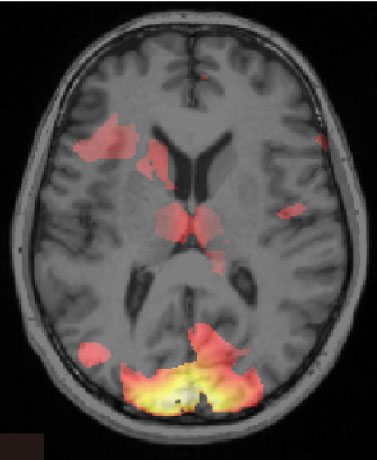

Escáner cerebral que muestra información asociada con un recuerdo de miedo. Imagen: Ai Koizumi. Fuente: Universidad de Cambridge.

El equipo ha desarrollado concretamente un método para identificar un recuerdo de miedo en el que se usa una nueva técnica llamada "Decoded Neurofeedback". Esta técnica utiliza escáneres cerebrales para registrar la actividad cerebral de un individuo y para identificar en ella patrones complejos vinculados con una memoria de miedo específica.